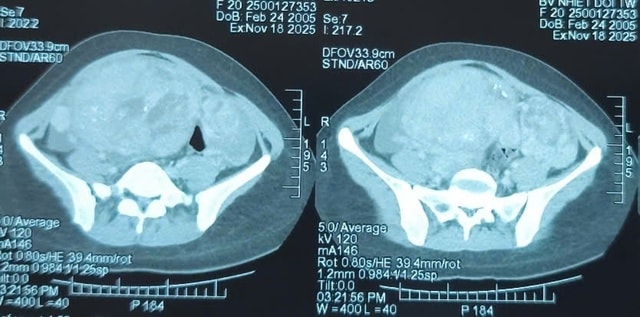

Khám lâm sàng ghi nhận một khối bất thường lớn tại vùng hạ vị. Kết quả chụp cắt lớp vi tính cho thấy khối u kích thước 110 x 163 x 244mm, bờ không đều, bên trong có nốt vôi hóa và xuất hiện dịch tự do trong ổ bụng. Bệnh nhân được chỉ định phẫu thuật cắt bỏ toàn bộ khối u.

Ngay khi mở ổ bụng, bác sĩ Trần Duy Hiến cho biết ông "không khỏi bất ngờ" khi nhìn thấy một khối u buồng trứng khổng lồ chiếm gần như toàn bộ vùng bụng dưới. Khối u căng tròn, phì đại bất thường ở cả hai bên vòi trứng và chèn ép mạnh lên tử cung.